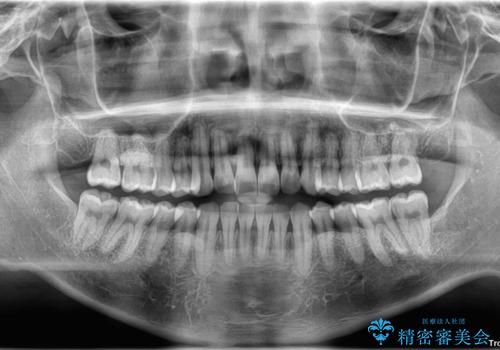

診察したところ、上下顎前歯部に軽度の叢生(ガタつき)が認められます。

目立たない装置を希望されたのでインビザライン ライトパッケージで治療を行うことになりました。